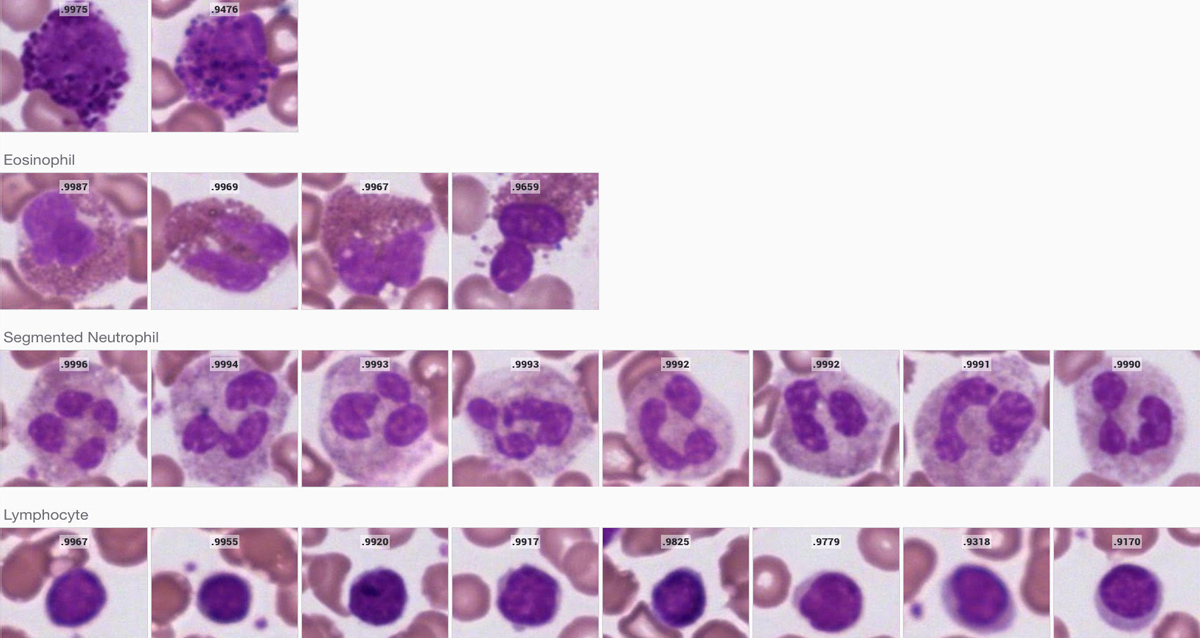

The Techcyte Blood Differential uses deep machine learning to identify in 30 seconds the mono layer, and classifies white blood cells and red blood cells into the following categories:

• Segmented neutrophils

• Eosinophils

• Lymphocytes

• Monocytes